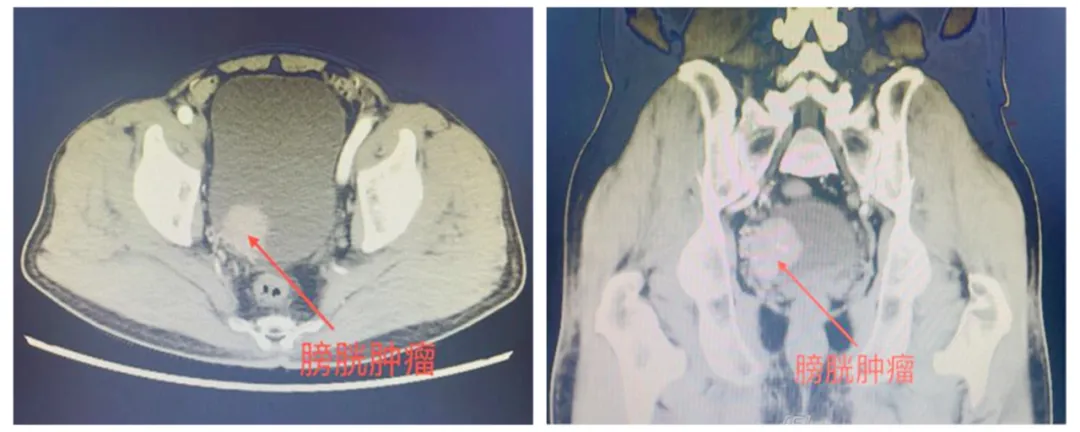

患者入院后完善下腹部+盆腔增强CT提示:膀胱右侧壁占位,考虑膀胱恶性肿瘤并侵犯右侧输尿管膀胱壁内段。进一步完善盆腔增强磁共振提示:膀胱右后壁可见一菜花状向腔内生长软组织肿块,大小约36mmX30mmX35mm,病变覆盖右侧输尿管膀胱壁内段,进一步完善膀胱镜活检提示:膀胱乳头状尿路上皮癌,浸润肌层。患者家属听闻膀胱肿瘤侵犯肌层需切除整个膀胱,并可能需要长期留置造口袋引流尿液后十分担心,向毕学成主任提出能否有好的手术方案,既能达到根治肿瘤的效果,又方便患者术后生活的护理。

▲患者术前泌尿系增强CT结果